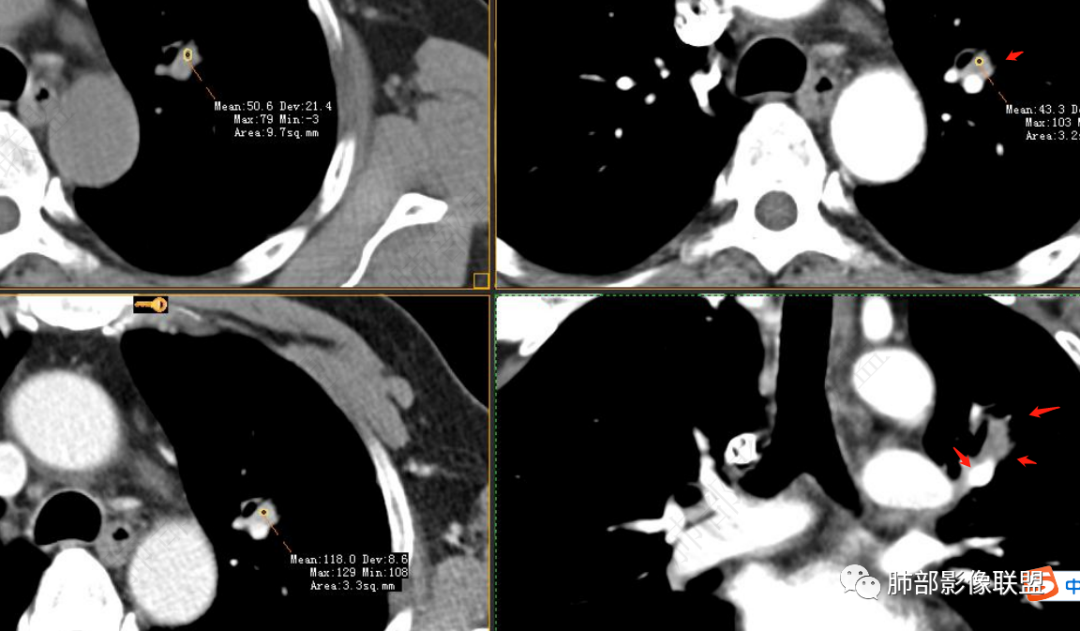

软组织+重建;病灶实性部分不是类圆形,密度相对均匀柔和。

肺门区病灶与支气管关系不密切,强化显著、磨玻璃晕等等容易想到的是肺腺癌。而不首先考虑与支气管密切相关恶性肿瘤,如鳞癌、类癌、粘液表皮样癌等等。

1、良性肿瘤——PSP,符合点实性部分强化明显,伴出血,周围长期GGO。不符合点:占位效应不够,对附近支气管无明显推移,整体形态非类圆形。生长太快。此外病灶的GGO,在前外,内侧没有,应该周围都有,不符合。